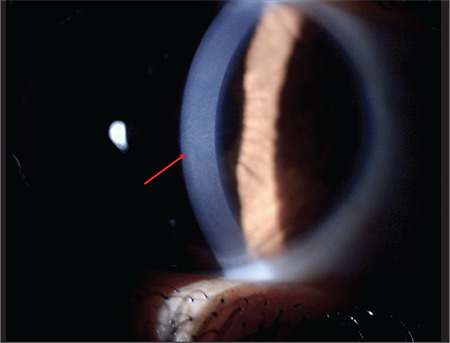

Materials and methods: This prospective, cross-sectional study included 30 eyes of 15 patients with FD. The diagnosis of FD was made based on a combination of clinical findings, genetic analysis, and biochemical evaluation. All participants underwent a detailed ophthalmic examination with special focus on the typical ocular features of FD (cornea verticillata, conjunctival aneurysms, cataract, retinal vessel tortuosity).

Results: The mean age was 45±17 years (range: 22-75 years), with a female/male ratio of 2:3. All patients had tortuous conjunctival vessels and 12 patients (80%) had conjunctival aneurysms. Cornea verticillata was present in 10 patients (66.6%), lens opacification in 4 patients (26.6%), and retinal vascular tortuosity in 8 patients (53.3%). All patients had at least two different ocular findings; most (3 heterozygotes/7 hemizygotes) had a combination of corneal verticillata and conjunctival vessel abnormality. The conjunctiva, cornea, and retina were affected together in 5 hemizygous patients (33.3%). One hemizygous patient had all FDrelated ocular manifestations in both eyes.

Conclusion: To our knowledge, this study is the first to describe the ocular manifestations of FD in the Turkish population. Although cornea verticillata is considered a hallmark of FD, it was absent in approximately one-third of patients. Moreover, cataract, another well-known feature of FD, was present in only 26.6% of the patients. Conjunctival vascular abnormality alone seems to be quite rare in FD, although it often accompanies other ocular manifestations. Therefore, recognition of other mild findings and special consideration of their associations may increase the diagnostic value of ocular findings in FD.